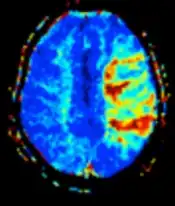

| Diffusion weighted (DWI) | Conventional | DWI | Measure of Brownian motion of water molecules.[17] | High signal within minutes of cerebral infarction (pictured).[18] |

|

Diffusion weighted

Diffusion MRI measures the diffusion of water molecules in biological tissues.[41] Clinically, diffusion MRI is useful for the diagnoses of conditions (e.g., stroke) or neurological disorders (e.g., multiple sclerosis), and helps better understand the connectivity of white matter axons in the central nervous system.[42] In an isotropic medium (inside a glass of water for example), water molecules naturally move randomly according to turbulence and Brownian motion. In biological tissues however, where the Reynolds number is low enough for laminar flow, the diffusion may be anisotropic. For example, a molecule inside the axon of a neuron has a low probability of crossing the myelin membrane. Therefore, the molecule moves principally along the axis of the neural fiber. If it is known that molecules in a particular voxel diffuse principally in one direction, the assumption can be made that the majority of the fibers in this area are parallel to that direction.

The recent development of diffusion tensor imaging (DTI)[43] enables diffusion to be measured in multiple directions, and the fractional anisotropy in each direction to be calculated for each voxel. This enables researchers to make brain maps of fiber directions to examine the connectivity of different regions in the brain (using tractography) or to examine areas of neural degeneration and demyelination in diseases like multiple sclerosis.

Another application of diffusion MRI is diffusion-weighted imaging (DWI). Following an ischemic stroke, DWI is highly sensitive to the changes occurring in the lesion.[44] It is speculated that increases in restriction (barriers) to water diffusion, as a result of cytotoxic edema (cellular swelling), is responsible for the increase in signal on a DWI scan. The DWI enhancement appears within 5–10 minutes of the onset of stroke symptoms (as compared to computed tomography, which often does not detect changes of acute infarct for up to 4–6 hours) and remains for up to two weeks. Coupled with imaging of cerebral perfusion, researchers can highlight regions of "perfusion/diffusion mismatch" that may indicate regions capable of salvage by reperfusion therapy.